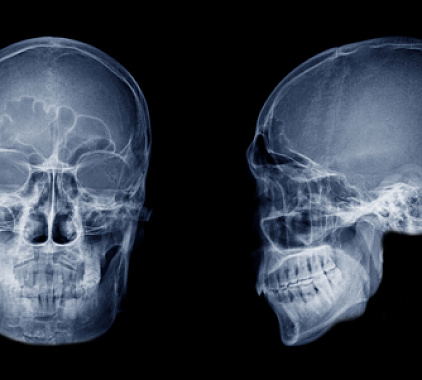

- Позиционирование. Голову фиксируют так, чтобы луч прошел строго через интересующую область. Чаще всего выполняют стандартный набор, куда входит и рентген пазух носа 2 проекции (подбородочно-носовая и затылочно-подбородочная). При сложных случаях добавляют боковой ракурс и позицию с открытым ртом.

Результаты рентгенографии околоносовых придаточных пазух

Врач анализирует снимок последовательно: сначала изучает норму, затем ищет отклонения.

Нормальная картина:

- Лобный и верхнечелюстной синусы выглядят как симметричные воздушные треугольники с ровными костными стенками.

- Решетчатый лабиринт содержит тонкие перегородки, а клиновидная полость занимает центральное положение.

- Контуры прозрачны, уровней жидкости нет, слизистая не утолщена.

Типичные патологические находки:

- Горизонтальный уровень жидкости. Свидетельствует об остром гнойном гайморите либо фронтите; важно срочно назначать антибактериальную терапию.

- Диффузное затемнение синуса. Чаще всего указывает на кисту, полипозное разрастание или грибковое поражение; без КТ уточнить границы образования сложно.

- Утолщение костной стенки, нарушение контура. Возможный признак хронического воспаления, доброкачественной остеомы или малигнизации.

- Смещенные фрагменты кости. Диагностируются при свежем или давнем переломе, требуют консультации челюстно-лицевого хирурга.

- Рентген-плотная тень в газовой полости. Может означать инородное тело; решение о хирургическом удалении принимают после осмотра ЛОР-врача.

Благодаря такому анализу рентген околоносовых пазух носа позволяет уточнить диагноз, выбрать метод лечения, а затем контролировать динамику без избыточной лучевой нагрузки. При необходимости второй рентген пазух носа спустя 7–10 дней показывает, насколько эффективно работает назначенная схема терапии.